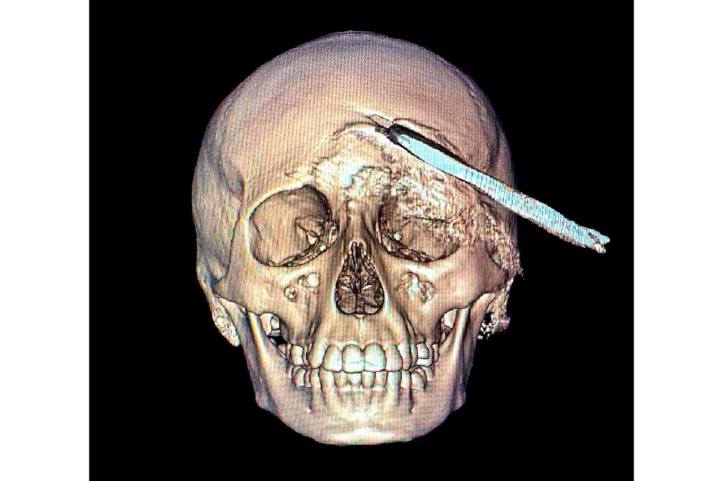

Tras confirmarse un traumatismo craneoencefálico severo, se realizaron estudios inmediatos que determinaron la profundidad y ubicación del objeto. Ante la complejidad del caso, el neurocirujano Elías Sinahí Ramírez Sánchez determinó que el adolescente debía ser trasladado a la T-1, que cuenta con el equipo necesario para una intervención especializada.

Los estudios de imagen permitieron ubicar con precisión el objeto, mientras el menor recibía tratamiento con antibióticos de amplio espectro para prevenir infecciones asociadas con el instrumento metálico.

Después de un análisis minucioso y una planeación quirúrgica, el doctor Ornelas González dirigió un procedimiento de cuatro horas que permitió retirar exitosamente la coa sin afectar tejido cerebral, en una intervención que confirmó la pericia y capacidad del equipo médico.